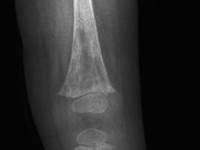

![Mafucci syndroom (click on photo to enlarge) [source: Miki Tanioka - www.intechopen.com - Creative Commons License 3.0] Mafucci syndroom](../../../images/mafucci-syndroom-2z.jpg) |

| Maffucci

syndroom |

Maffucci

Foto's: Miki Tanioka - Mafucci syndrome -

www.intechopen.com (Creative Commons License

3.0).